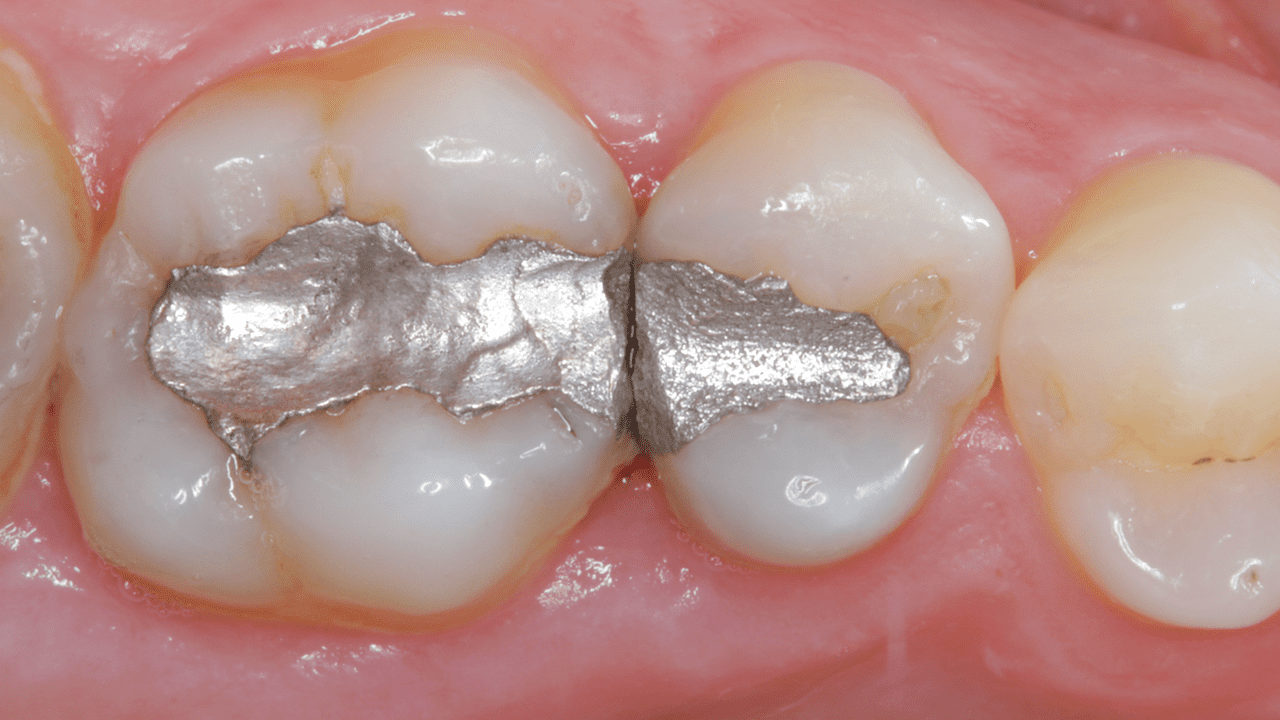

Case: Initial case showing defective and leaking old amalgam restorations.